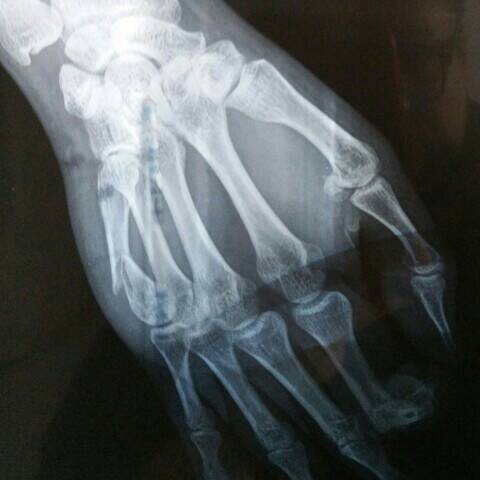

本图片仅供参考